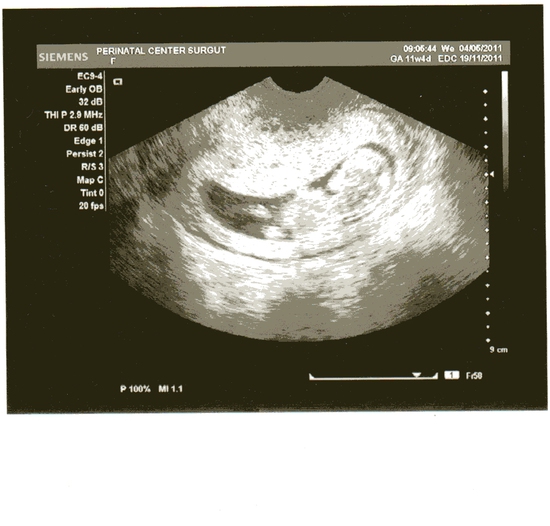

Приплыли.:-( После счастливого «ничего вообще не ощущаю», вчера, на 11 неделе, меня ожидал неприятный сюрпризец в виде крови. Случилось сие после работы, благо, что до больницы недалеко — дошла быстренько. Из хорошего: оба детища видны на УЗИ (один из них «догнал» другого по размерам, на 7 неделе он отставал немного). Сердцебиения нормальные, шейка закрыта, какие-то тесты крови делались (подозреваю, что ХГЧ) — в норме. Из нехорошего: врач достала два солидных шмотка свернувшейся крови и сегодня кровь медленно, но верно продолжает идти, коричнево-красного цвета. Как прочла в инернете: шансы 50/50 у нас. И что бы я ни делала — от меня исход не зависит. Врач тоже развела руками и сказала — ждать. Вопрос, который меня интересует и на который мне не дали ответа в больнице: какие могут быть причины кровотечения? Позитивные истории тоже принимаются, для поддержания боевого духа…:-)

Нет. Но УЗИ, надо сказать, было не супер по качеству.